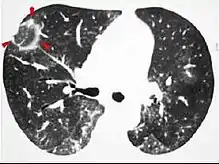

- Lung adenocarcinomaCT image showing diffuse GGOs throughout both lungs. An abscess is also noted in the right lung (screen left).

The diffuse pattern typically refers to GGOs in multiple lobes of one or both lungs. Broadly, a diffuse pattern of GGO can be caused by displacement of air with fluid, inflammatory debris, or fibrosis. Cardiogenic pulmonary edema and ARDS are common causes of a fluid-filled lung. Diffuse alveolar hemorrhage is a rarer cause of diffuse GGO seen in some types of vasculitis, autoimmune conditions, and bleeding disorders.[6]

Inflammation and fibrosis can also cause diffuse GGOs. Pneumocystis pneumonia, an infection typically seen in immunocompromised (e.g. patients with AIDS) or immunosuppressed individuals, is a classic cause of diffuse GGOs. Many viral pneumonias and idiopathic interstitial pneumonias can also lead to a diffuse GGO pattern. Radiation pneumonitis, a side effect of pulmonary radiation therapy, can lead to pulmonary fibrosis and diffuse GGOs.[6]